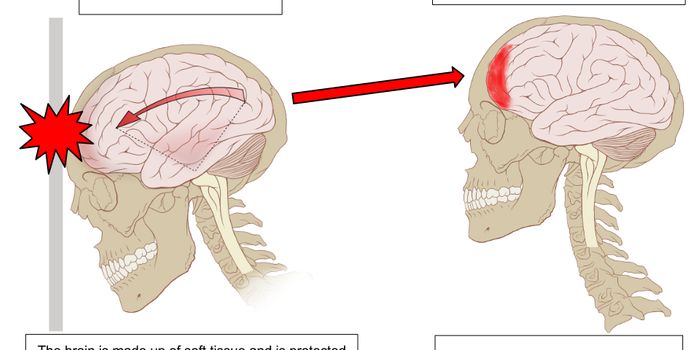

OCT 07, 2015NeuroscienceThe NFL is known for a lot of things. Big players tackling each other, cheerleaders, the Super Bowl, and sadly, for inju ...